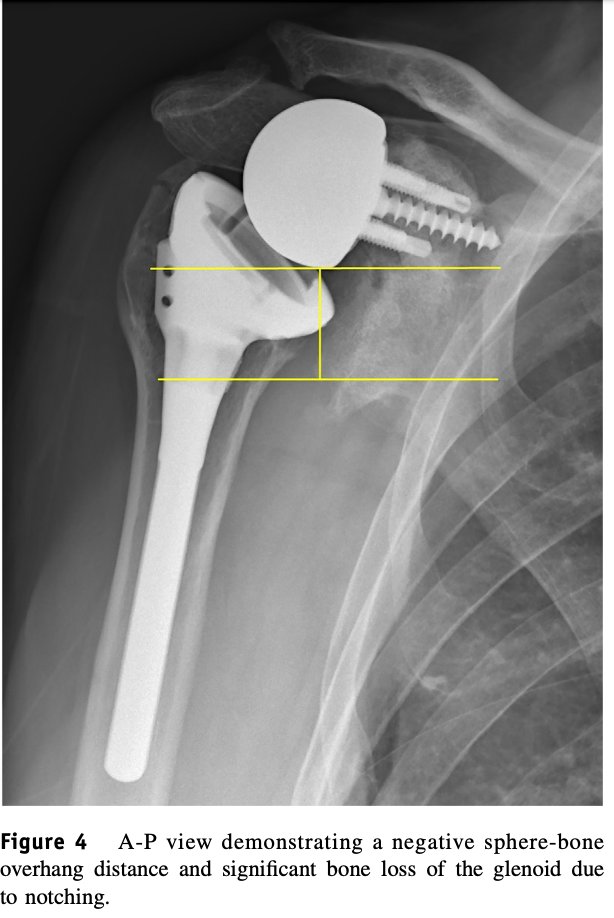

Four recently published articles provide important new information about the ream and run procedure for active patients with shoulder arthritis Those readers interested in learning more can access a discussion of these new articles here: shoulderarthritis.blogspot.com/2026/03/cocr-r…